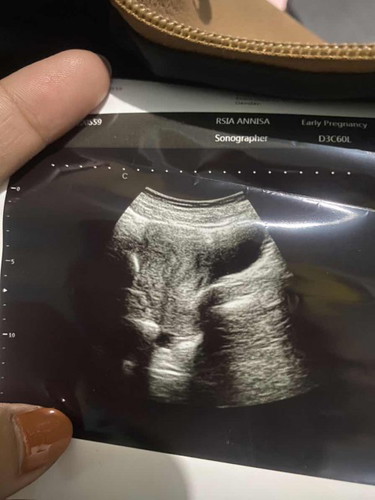

tentang kehamilan

saya usg kenapa blum nampak tp tespek udh positif

masih 4week biasa nya ada yg udah keliatan kantung nya bunda, kalo liat janin itu di 8 week arahan dari dokter seperti itu bun :) semoga membantu

janin baru keliatan gumpalan kecil aja pas usia 4 minggu.